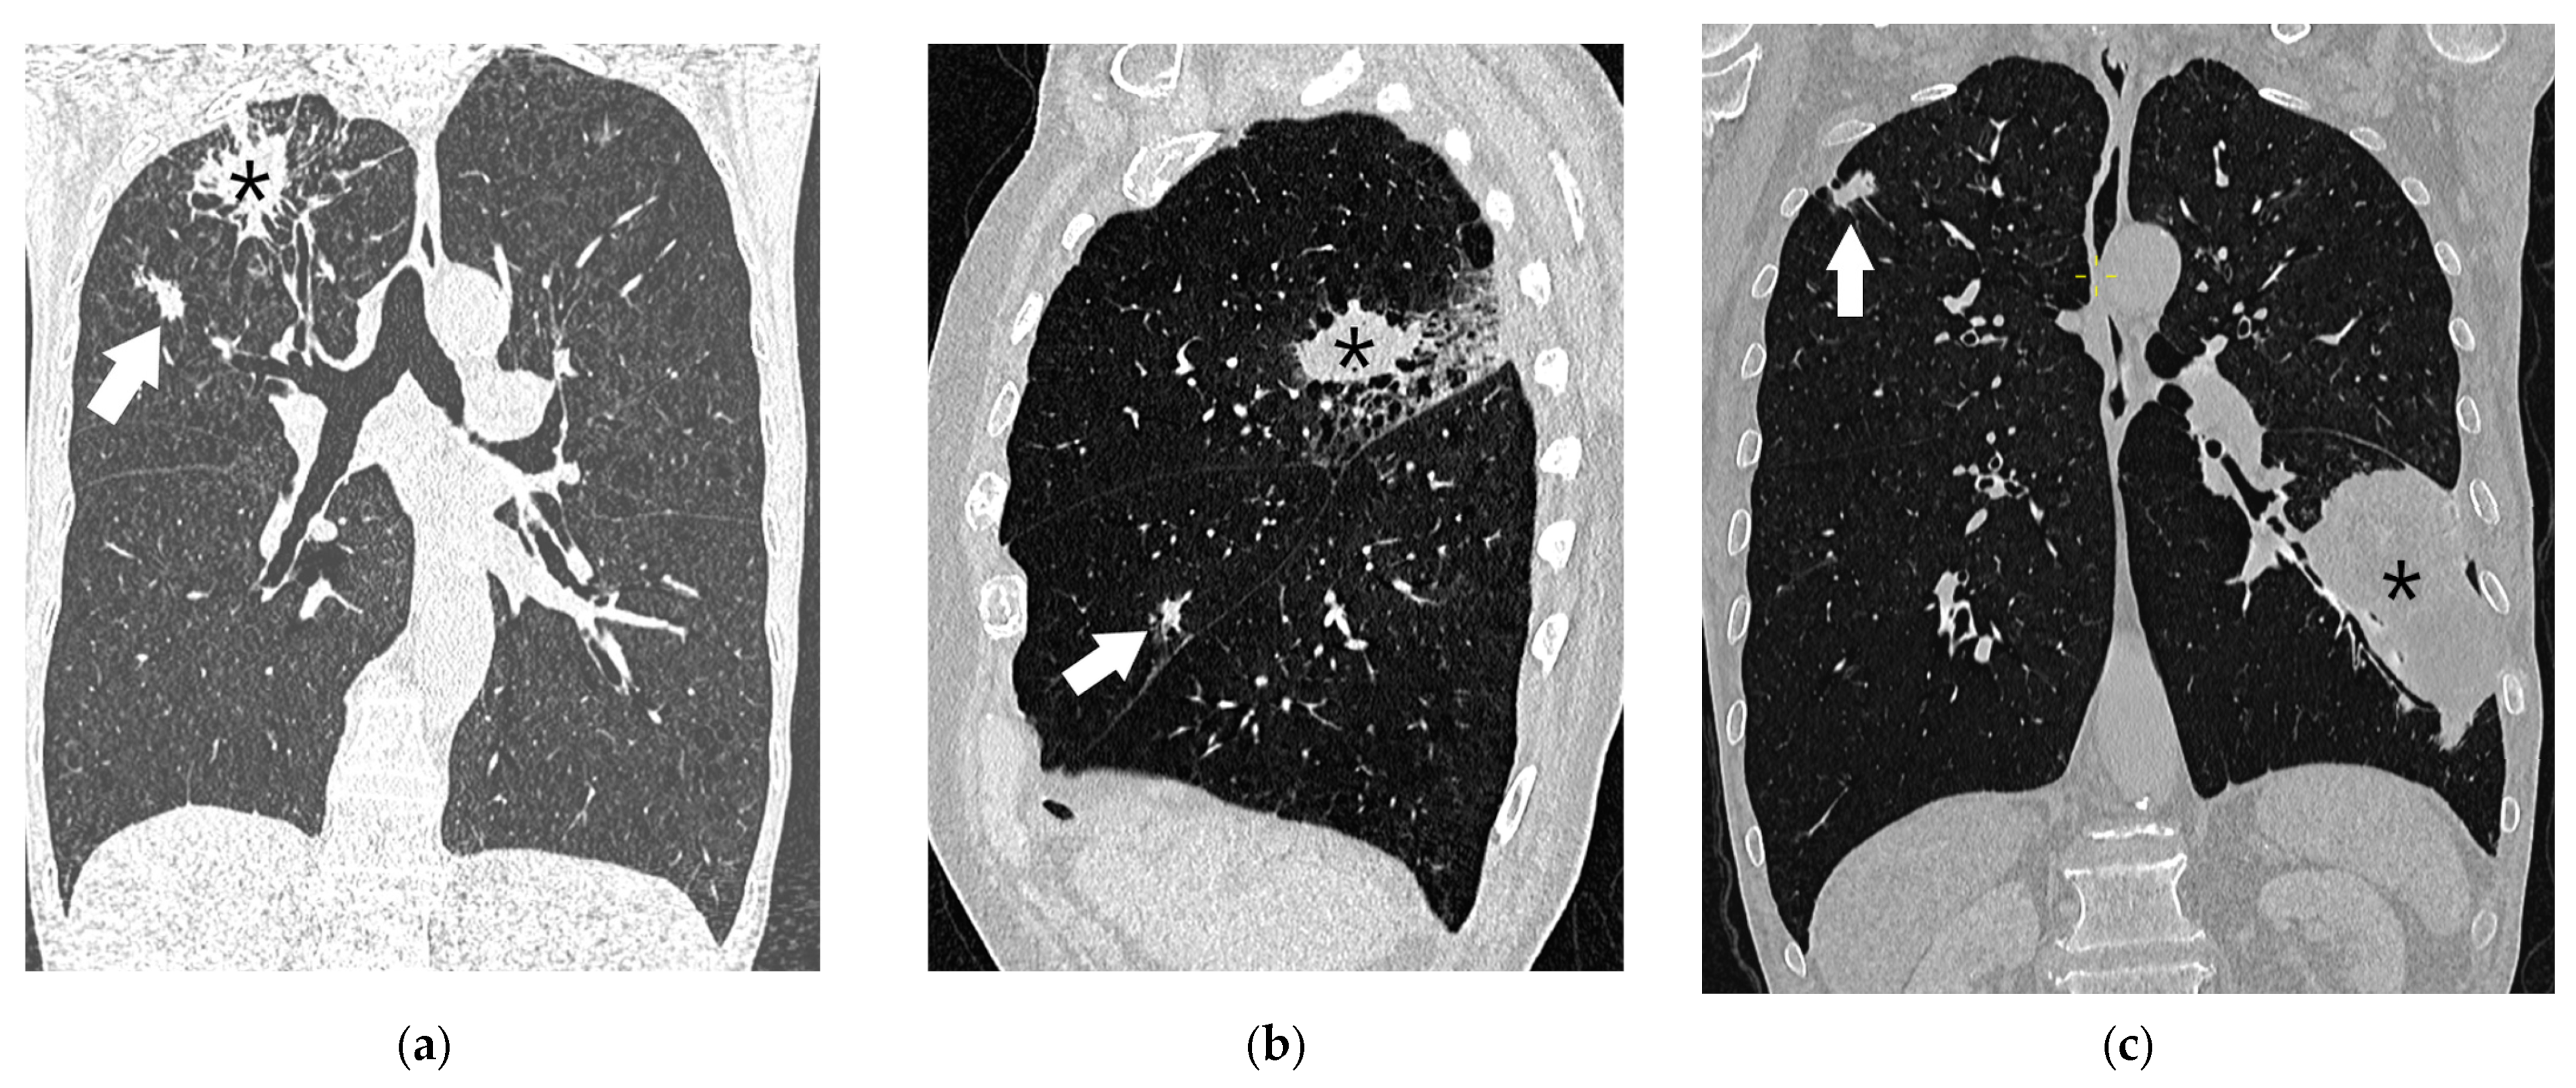

- In patients with a solid primary lung cancer with one or more separate solid tumor nodule(s) of the same histological type, separate nodules are considered to be intrapulmonary metastases (Figure 15). The presence of separate tumor nodule(s) in the same lobe as the primary tumor indicates T3 disease. If there are separate tumor nodules in a different ipsilateral lobe than that of the primary tumor, stage T4 should be determined. Lung nodules in the contralateral lung indicate distant metastases (M1a disease). Although the classification of multiple lung nodules in lung cancer patients may appear simple, it may lead to overstaging if lesions are not confirmed histologically, since the majority of lung nodules identified in patients with lung cancer are benign [37].

- Multiple lung cancer nodules with prominent ground-glass or lepidic features should be classified according to the highest T lesion. The lesion size is determined by the largest diameter of the solid component at CT. The number of lesions (#), or simply (m) for multiplicity, should be indicated in parentheses after the T descriptor of the highest lesion. This approach should be applied equally for lesions with ground-glass or lepidic features located in the same lobe or different ipsilateral or contralateral lobes. An N and M category should be applied to all lesions collectively with a single N and M stage.

- Pneumonic-type lung cancer has a consolidative pattern on CT in the absence of an obstructed bronchus. It should be categorized as T3 if confined to a single lobe, T4 if different ipsilateral lobes are involved, or M1a if contralateral lobes are involved. A T4 designation should be applied both if there is a direct extension into another lobe and when there is a discrete separate area of involvement in an adjacent lobe. Again, a single N and M category should be assigned for all lesions.